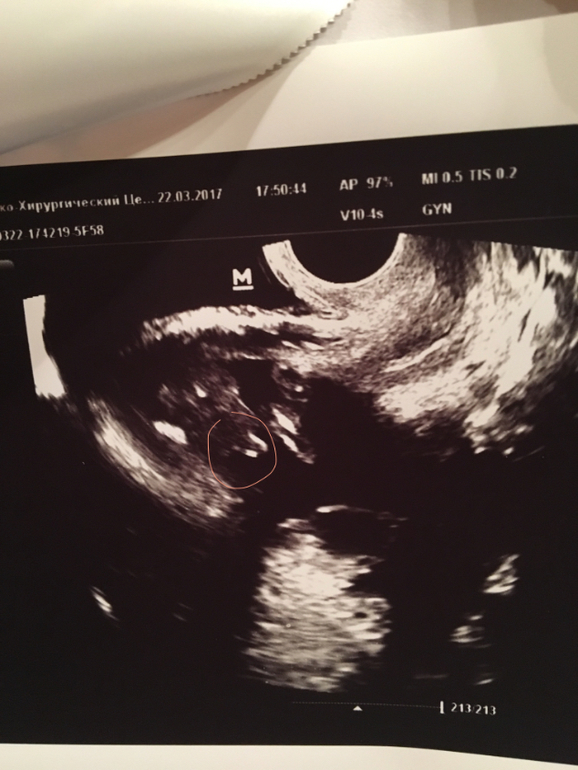

Пол малыша

Результаты: УЗИ, КТГ, доплера, скринингаДевочки, помогайте!

У кого глаз алмаз? Я ничего не понимаю, где чего у малыша . Выделила тк область, которая НА МОЙ ВЗГЛЯД, что-то говорит о поле маленького. (, 1фоткой мне вообще непонятно)

Фото под кат